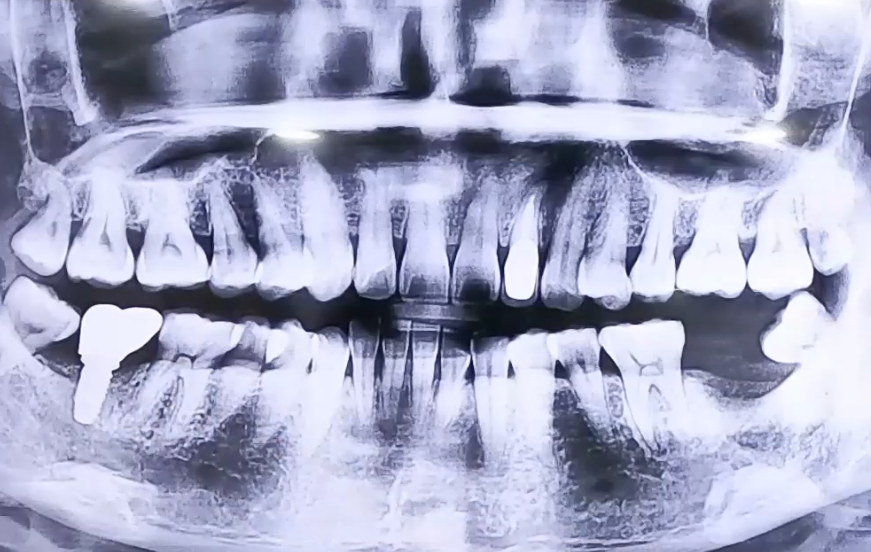

BEFORE

왼쪽 아래 가장 뒤쪽 사랑니 주변의 극심한 통증으로

주말에 급하게 방문해 주신 환자분이십니다.

사랑니가 앞쪽 어금니에 걸려 절반만 나와있고 기울어져 있었는데요.

그 때문에 주변으로 잇몸이 많이 부어 있는 상태이셨습니다.

엑스레이를 찍어보니 사랑니의 영향을 받아 사랑니 앞에 있는

정상 어금니 주변으로 염증이 너무 많이 생긴 것이 보였는데요.

이에 통증의 원인인 염증 부분의 치아와 사랑니를 발치하고

빈 상태였던 오른쪽 아래 어금니와 왼쪽 발치한 어금니 자리에

임플란트 식립을 하여 어금니의 기능을 복원해 드렸습니다.